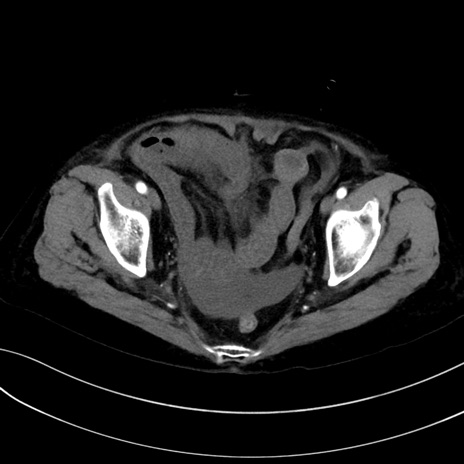

症例13 CT(横断像)1日半後